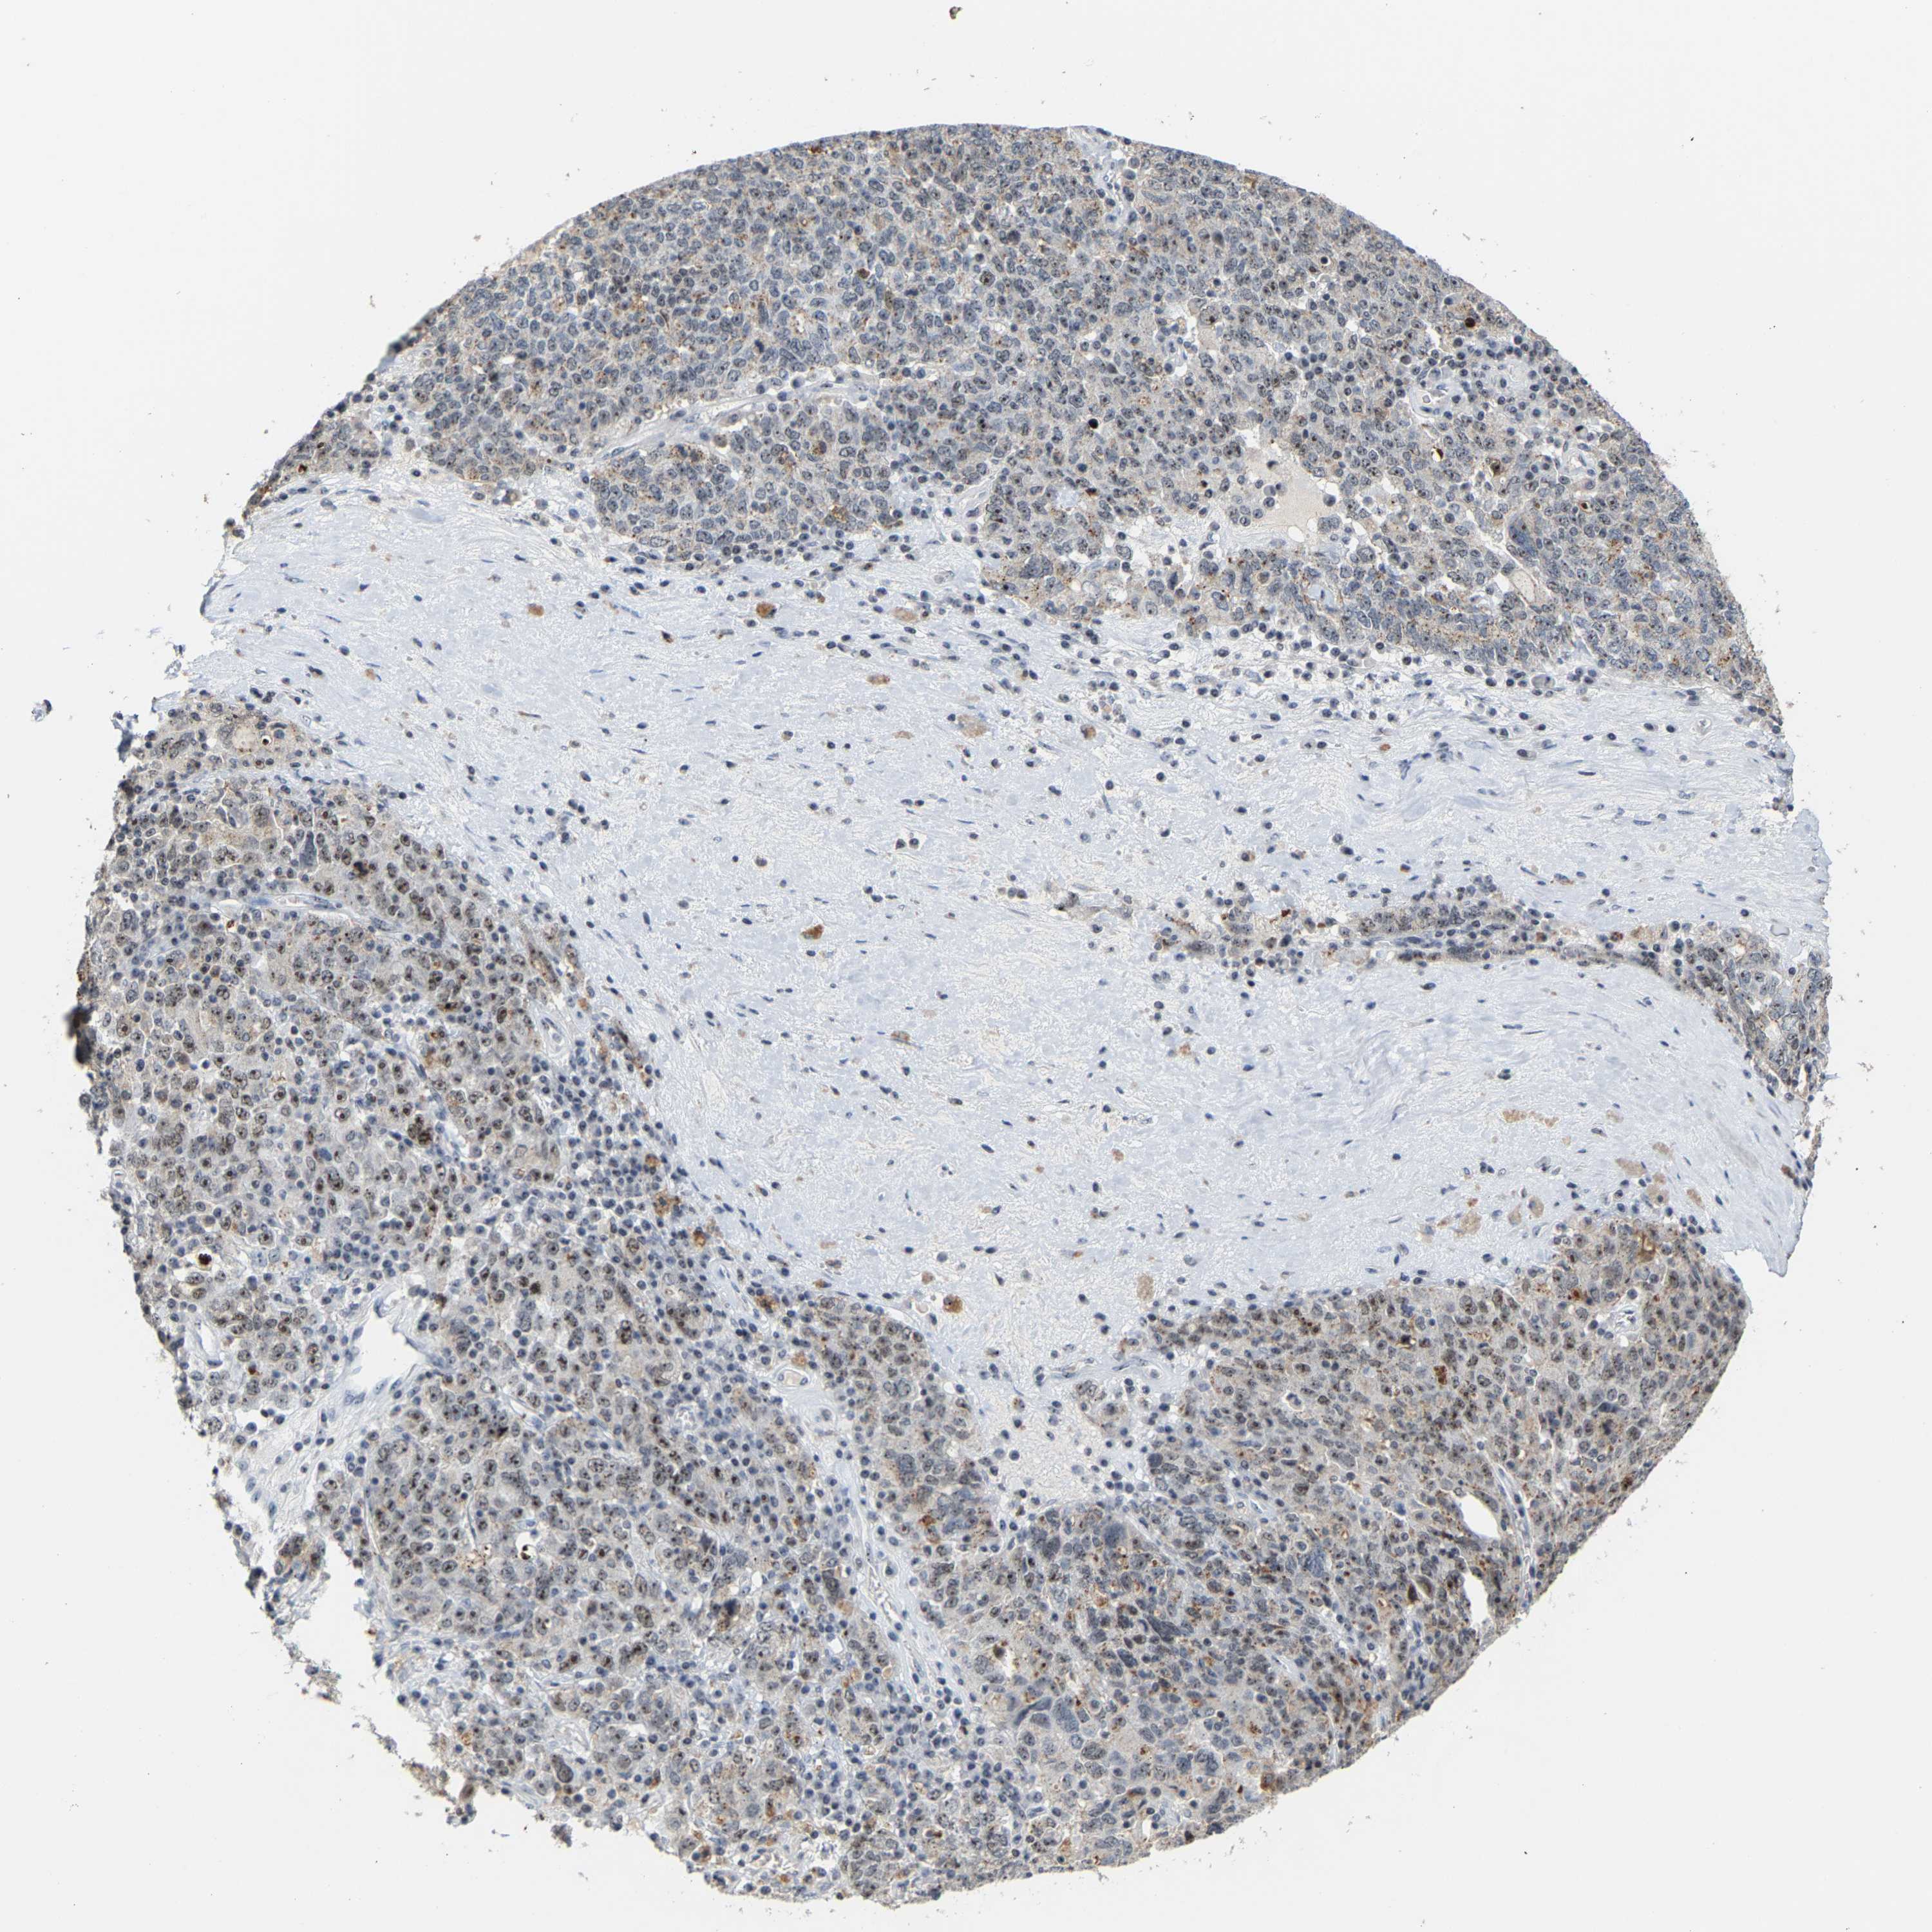

OVARIAN CANCER - Protein expressioni

A mouse-over function shows sample information and annotation data. Click on an image to view it in a full screen mode. Samples can be filtered based on level of antibody staining by selecting one or several of the following categories: high, medium, low and not detected. The assay and annotation is described here.

Note that samples used for immunohistochemistry by the Human Protein Atlas do not correspond to samples in the TCGA dataset.

Antibody stainingi

Antibody staining in the annotated cell types in the current human tissue is reported as not detected, low, medium, or high, based on conventional immunohistochemistry profiling in selected tissues. This score is based on the combination of the staining intensity and fraction of stained cells.

Each image is clickable and will lead to virtual microscopy that enables deeper exploration of all samples and also displays staining intensity scores, fraction scores and subcellular localization as well as patient and tissue information for each sample.

Antibody HPA018472

Antibody HPA021062

Staining

High

Medium

Low

Not detected

Intensity

Strong

Moderate

Weak

Negative

Quantity

>75%

75%-25%

<25%

None

Location

Nuclear

Cytoplasmic/membranous

Cytoplasmic/membranous,nuclear

Cystadenocarcinoma, serous, NOS

Carcinoma, endometroid

Cystadenocarcinoma, mucinous, NOS

Carcinoma, NOS